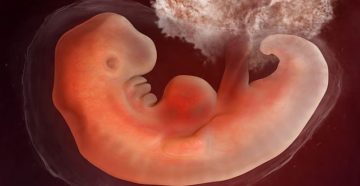

Как выглядит плод на 4 неделе беременности? Когда идёт 4 неделя беременности – это ощущается?…